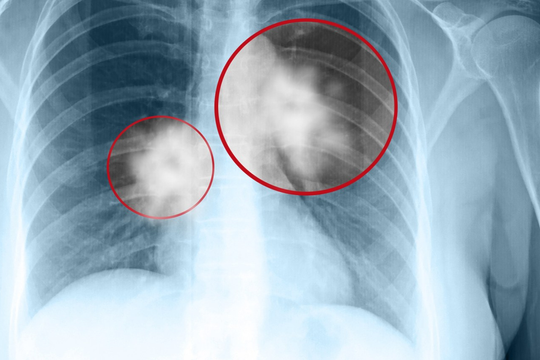

Ung thư phổi là gì?

Bài viết trên website Bệnh viện Đa khoa Tâm Anh có sự tư vấn chuyên môn của BS.CKI. Vũ Trần Minh Nguyên cho biết, theo Globocan 2020 (cơ sở dữ liệu ung thư của Cơ quan Nghiên cứu Ung thư Quốc tế), ung thư phổi là bệnh lý ung thư gây tử vong hàng đầu trên toàn thế giới và đứng thứ 2 tại Việt Nam.

Ung thư phổi được chia làm 2 nhóm chính: ung thư phổi không tế bào nhỏ (NSCLC: non–small cell lung cancer) và ung thư phổi tế bào nhỏ (SCLC: small cell lung cancer).

Ung thư phổi không tế bào nhỏ là loại ung thư phổi phổ biến nhất, chiếm 85% các trường hợp ung thư phổi. Trong đó, 3 loại giải phẫu bệnh thường gặp bao gồm: